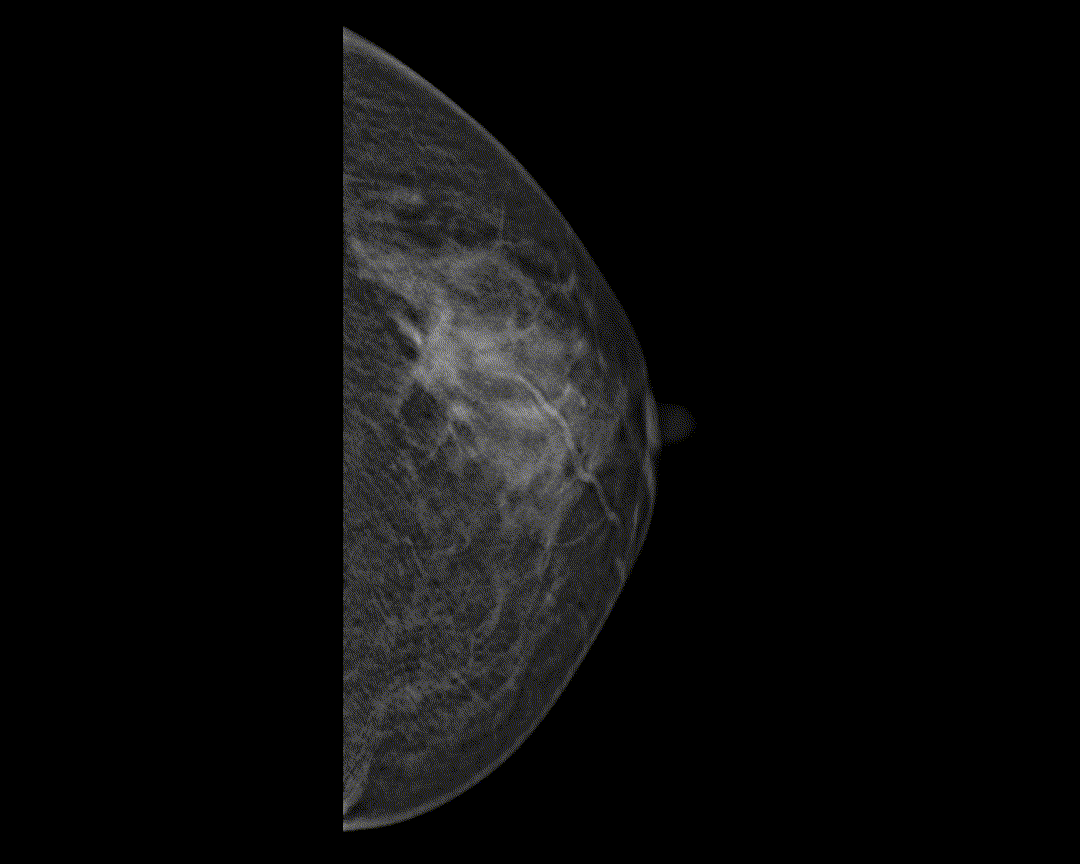

Adaptacyjne dostosowanie grubości warstwy tomosyntezy zapewnia szczegółowe obrazowanie przestrzenne zmian chorobowych i skupisk mikrozwapnień.

Hybrydowe protokoły wyświetlania pozwalają na synchroniczne wyświetlanie obrazów 2D i warstw tomosyntezy w celu łatwego porównania. Dostępne są zarówno pogrubione warstwy (slabs), jak i widok płaszczyzny.